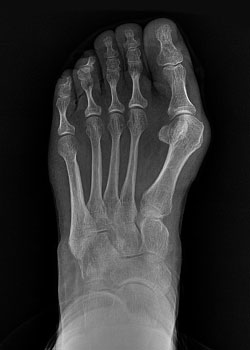

After